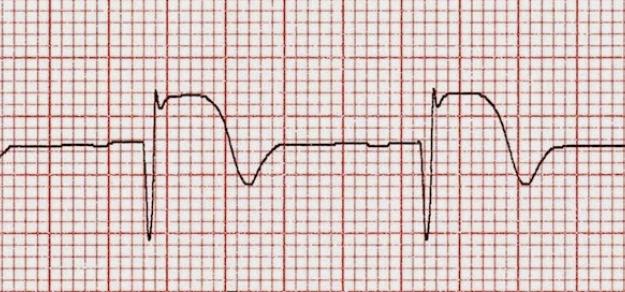

En pacientes que cursan un infarto de miocardio y elevación del segmento ST (IMEST), el medicamento chino patentado Tongxinluo, agregado a los tratamientos recomendados por las guías para IMEST, mejoró significativamente los resultados clínicos a 30 días y 1 año. Se necesitan más investigaciones para determinar el mecanismo de acción de Tongxinluo en el IMEST. JAMA, 24 de octubre de 2023.